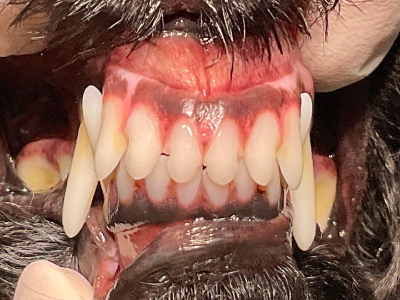

正常咬合

犬の正常咬合です。

人と同じように上の前歯が前、下の前歯が後ろに噛み合うのが一般的です。 -